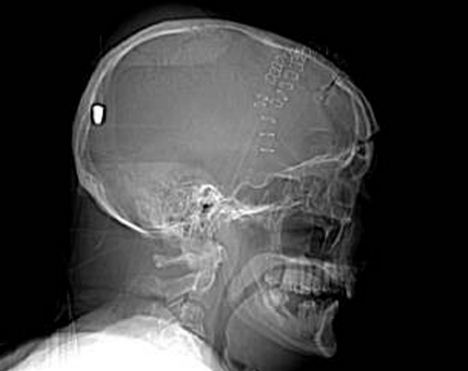

CT掃描顯示子彈留在彼得老人的腦部

據英國《每日郵報》5月11日報道,英國一名61歲的老人上個月19日在花園干活時被一顆流彈擊中腦部竟奇跡存活,目前他半身癱瘓但無生命危險。5月10日,警方為了破案公布了彼得先生的腦部掃描圖片,希望知情者提供相關線索。

事情的經過是這樣的,彼得在整理花園的時候突然摔倒在地不省人事,他的家人還以為他中風了,但醫院對其大腦掃描后卻發現了令人驚悚的事實:一顆子彈不知由于何種原因從左眼窩進入他的大腦,并深深植入其腦后部。但不可思議的是彼得竟然活了下來,雖然身體部分癱瘓且失去了語言和記憶能力。

醫生說開顱取彈手術風險巨大,很可能危及彼得生命,所以只能放棄這個計劃。彼得先生已經被告知事故經過,但他自己什么也想不起來了,醫生認為他患了健忘癥。除了損傷左眼視力外,彼得先生身體右下半部分也已癱瘓。他的發音都很含糊,記憶也是支離破碎的,目前大部分時間都在睡覺,但病情還算穩定。

負責調查此案的警官史蒂夫表示:“這可能是我調查過的最詭異的一個案子了。”經過對掃描圖片的鑒定,警方彈道專家賈爾斯認為這顆子彈很像是從一種通常用于射殺兔子的.22口徑獵槍里射出的。

“如果在10碼外開這種槍,子彈會穿透彼得的腦部,但若是從800到1000碼以外,子彈會失去大部分的沖擊力,只能穿透軟組織。所以說,在這個距離內,子彈若射中彼得腦殼會被彈回,不可能進入腦中,”賈爾斯說。